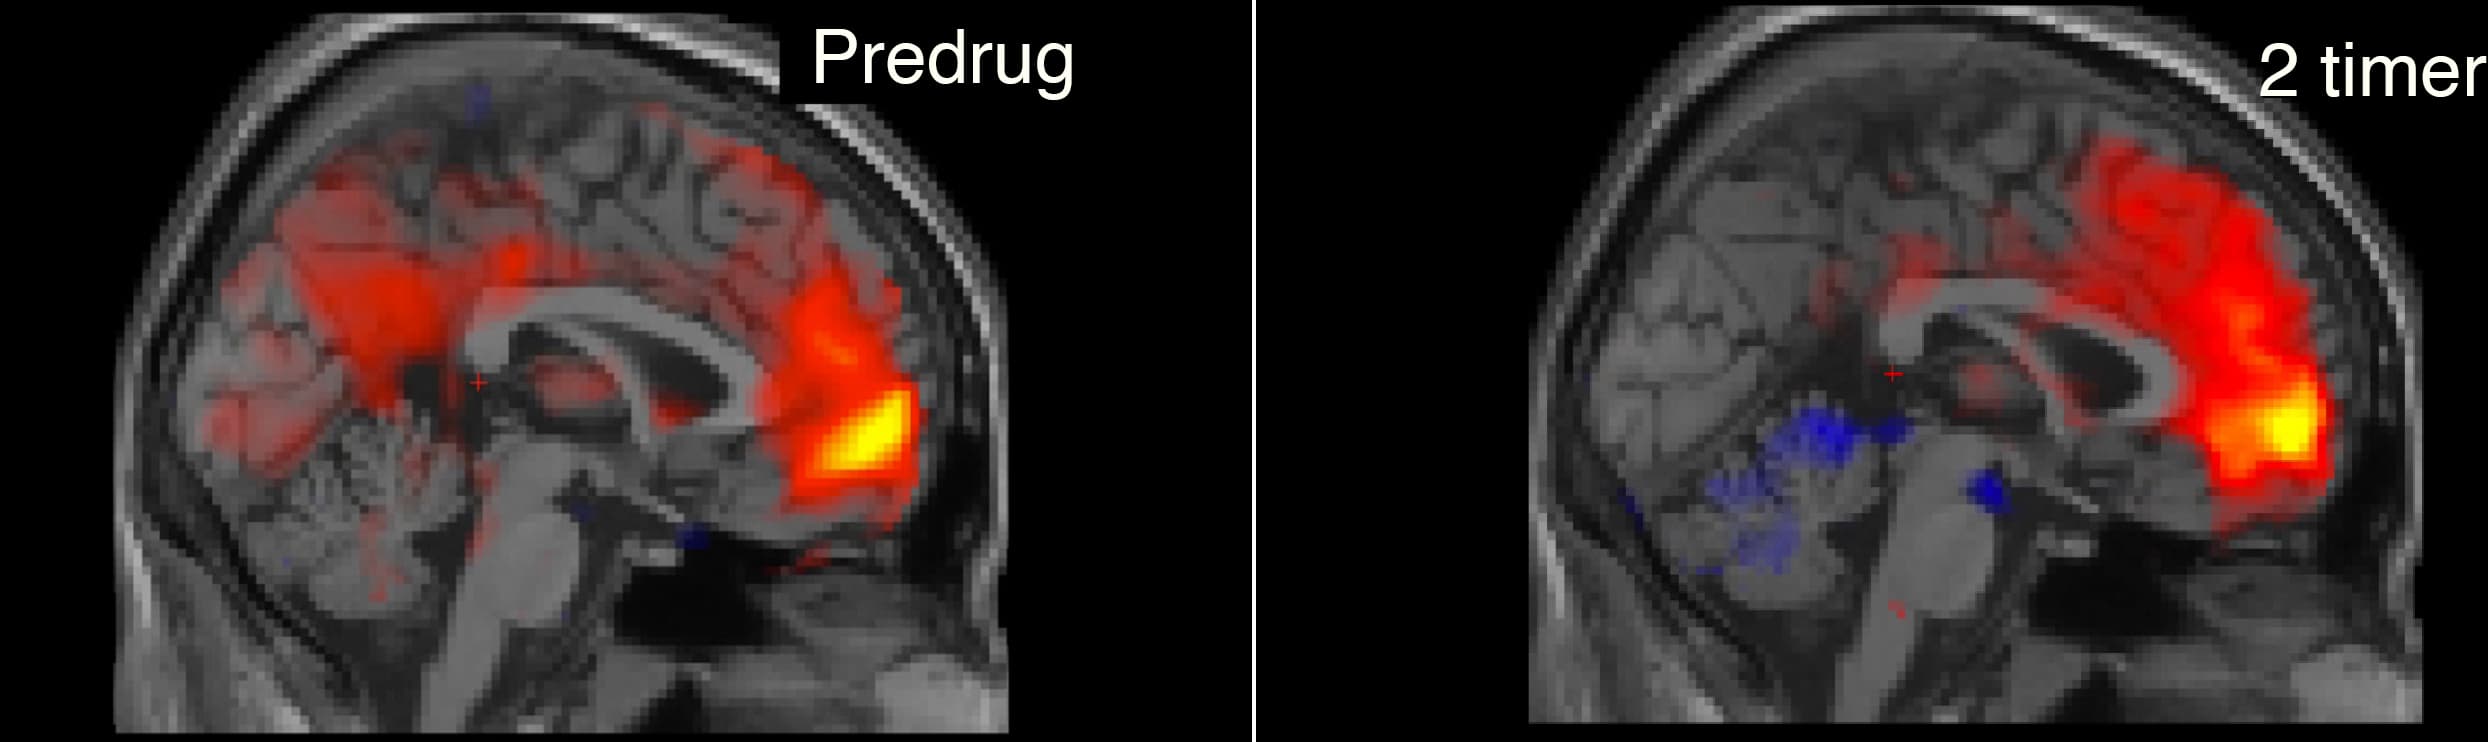

Tv.: fMRI-billedet viser funktionel konnektivitet mellem den mediale præfrontale cortex (MPFC) og resten af hjernen før indgift af psilocybin. Den røde farve i den posteriore cingulate cortex (PCC), viser positiv funktionel konnektivitet med MPFC. Th.: Funktionel konnektivitet for samme forsøgsperson to timer efter 18 mg psilocybin. Fraværet af rød farve i PCC viser markant nedsat funktionel konnektivitet med MPFC. MPFC og PCC er kernestrukturer i default-mode netværk, der er relateret til bla jegoplevelse. (Foto: (Kilde: Martin Korsbak Madsen))